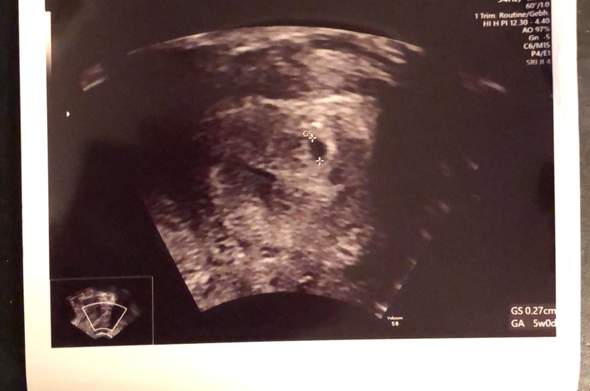

SSW dar, sondern erscheint leicht queroval Hier wurde zwar nicht gemessen, aber in Relation zur Gebärmuttergröße kann man den Durchmesser der Fruchthöhle auf ca einen Zentimeter schätzen Auch hier ist der Embryo noch nicht erkennbar Ultraschallbild 53 SSW Ein weiteres Ultraschallbild vom 3 der 6 Schwangerschaftswoche (53). 6 4 ssw ultraschall nur fruchthöhle Anzeichen, Symptome & Ultraschall in der 6 SSW In der 6 Schwangerschaftswoche kann im Ultraschall der Herzschlag des Babys bereits sichtbar werden, auf jeden Fall ist die Fruchthöhle als schwarzes Oval und der bohnenförmige Embryo erkennbar 6Schwangerschaftswoche (6. Ultraschall in der 61 SSW nur Fruchthöhle und Dottersack sichtbar Tamara92 1 0812 Uhr in Schwangerschaft Hallo zusammen Ich bin 28 Jahre und bin nach einer 2 jährigen Kinderwunschbehandlung während der ersten ICSI schwanger geworden🥰.

Und am 116 hatte ich einen positiven SSW Test Ich war dann auch gleich beim FA am 116 und er sah eine kleine Höhle von 0,33cm, Montag den 146 war ich wieder beim FA und er sah wieder eine Höhle von 0,70cm So, nun EINE WOCHE später, heute war ich wieder beim FA und wieder sah er nur die Fruchthöhle mit 0,94cm und aber. Bei mir hat man in der 5 Woche auch noch keine Fruchthöhle gesehen, nur die aufgebaute Gebärmutterschleimhaut und später ist dann raus gekommen, dass ich doch erst in der 4 Woche war und deshalb auf dem Ultraschall noch nichts zu sehen war!. SSW 60 nur Fruchthöhle, kein Embryo, kein Dottersack Maroni2701 schrieb am 1651 Registriert seit Beiträge 21 Hallo, ich bin im Moment sehr traurig Zuerst mag ich aber meinen Verlauf erzählen war mein erster der letzten Periode genau zwei Wochen danach hat der Clearblue Test angezeigt.

Heute war ich nun zum ersten Ultraschall (vaginal) und es war leider nur eine leere Fruchthöhle, aber kein Dottersack und auch kein Embryo zu sehen Der HCGWert war bei Praxisschluss leider noch nicht fertig (musste laut Schwester noch "verdünnt werden") läge aber angeblich bei über 5000 Den genauen Wert erfahre ich morgen früh. War am 247 beim Frauenarzt, da war ich laut Rechnung 55 ssw Man konnte nur eine leere fruchthöhle erkennen. 5 ssw ultraschall nur fruchthöhle Schwangerschaft 6 Woche (6 SSW) Ultraschallbilde Hier sieht man deutlich die schwarze Fruchthöhle, der Embryo lässt sich noch nicht erkennenMan sieht aber ebenfalls sehr deutlich, dass es sehr darauf ankommt, wie der Arzt bei der Untersuchung die Messpunkte setzt.